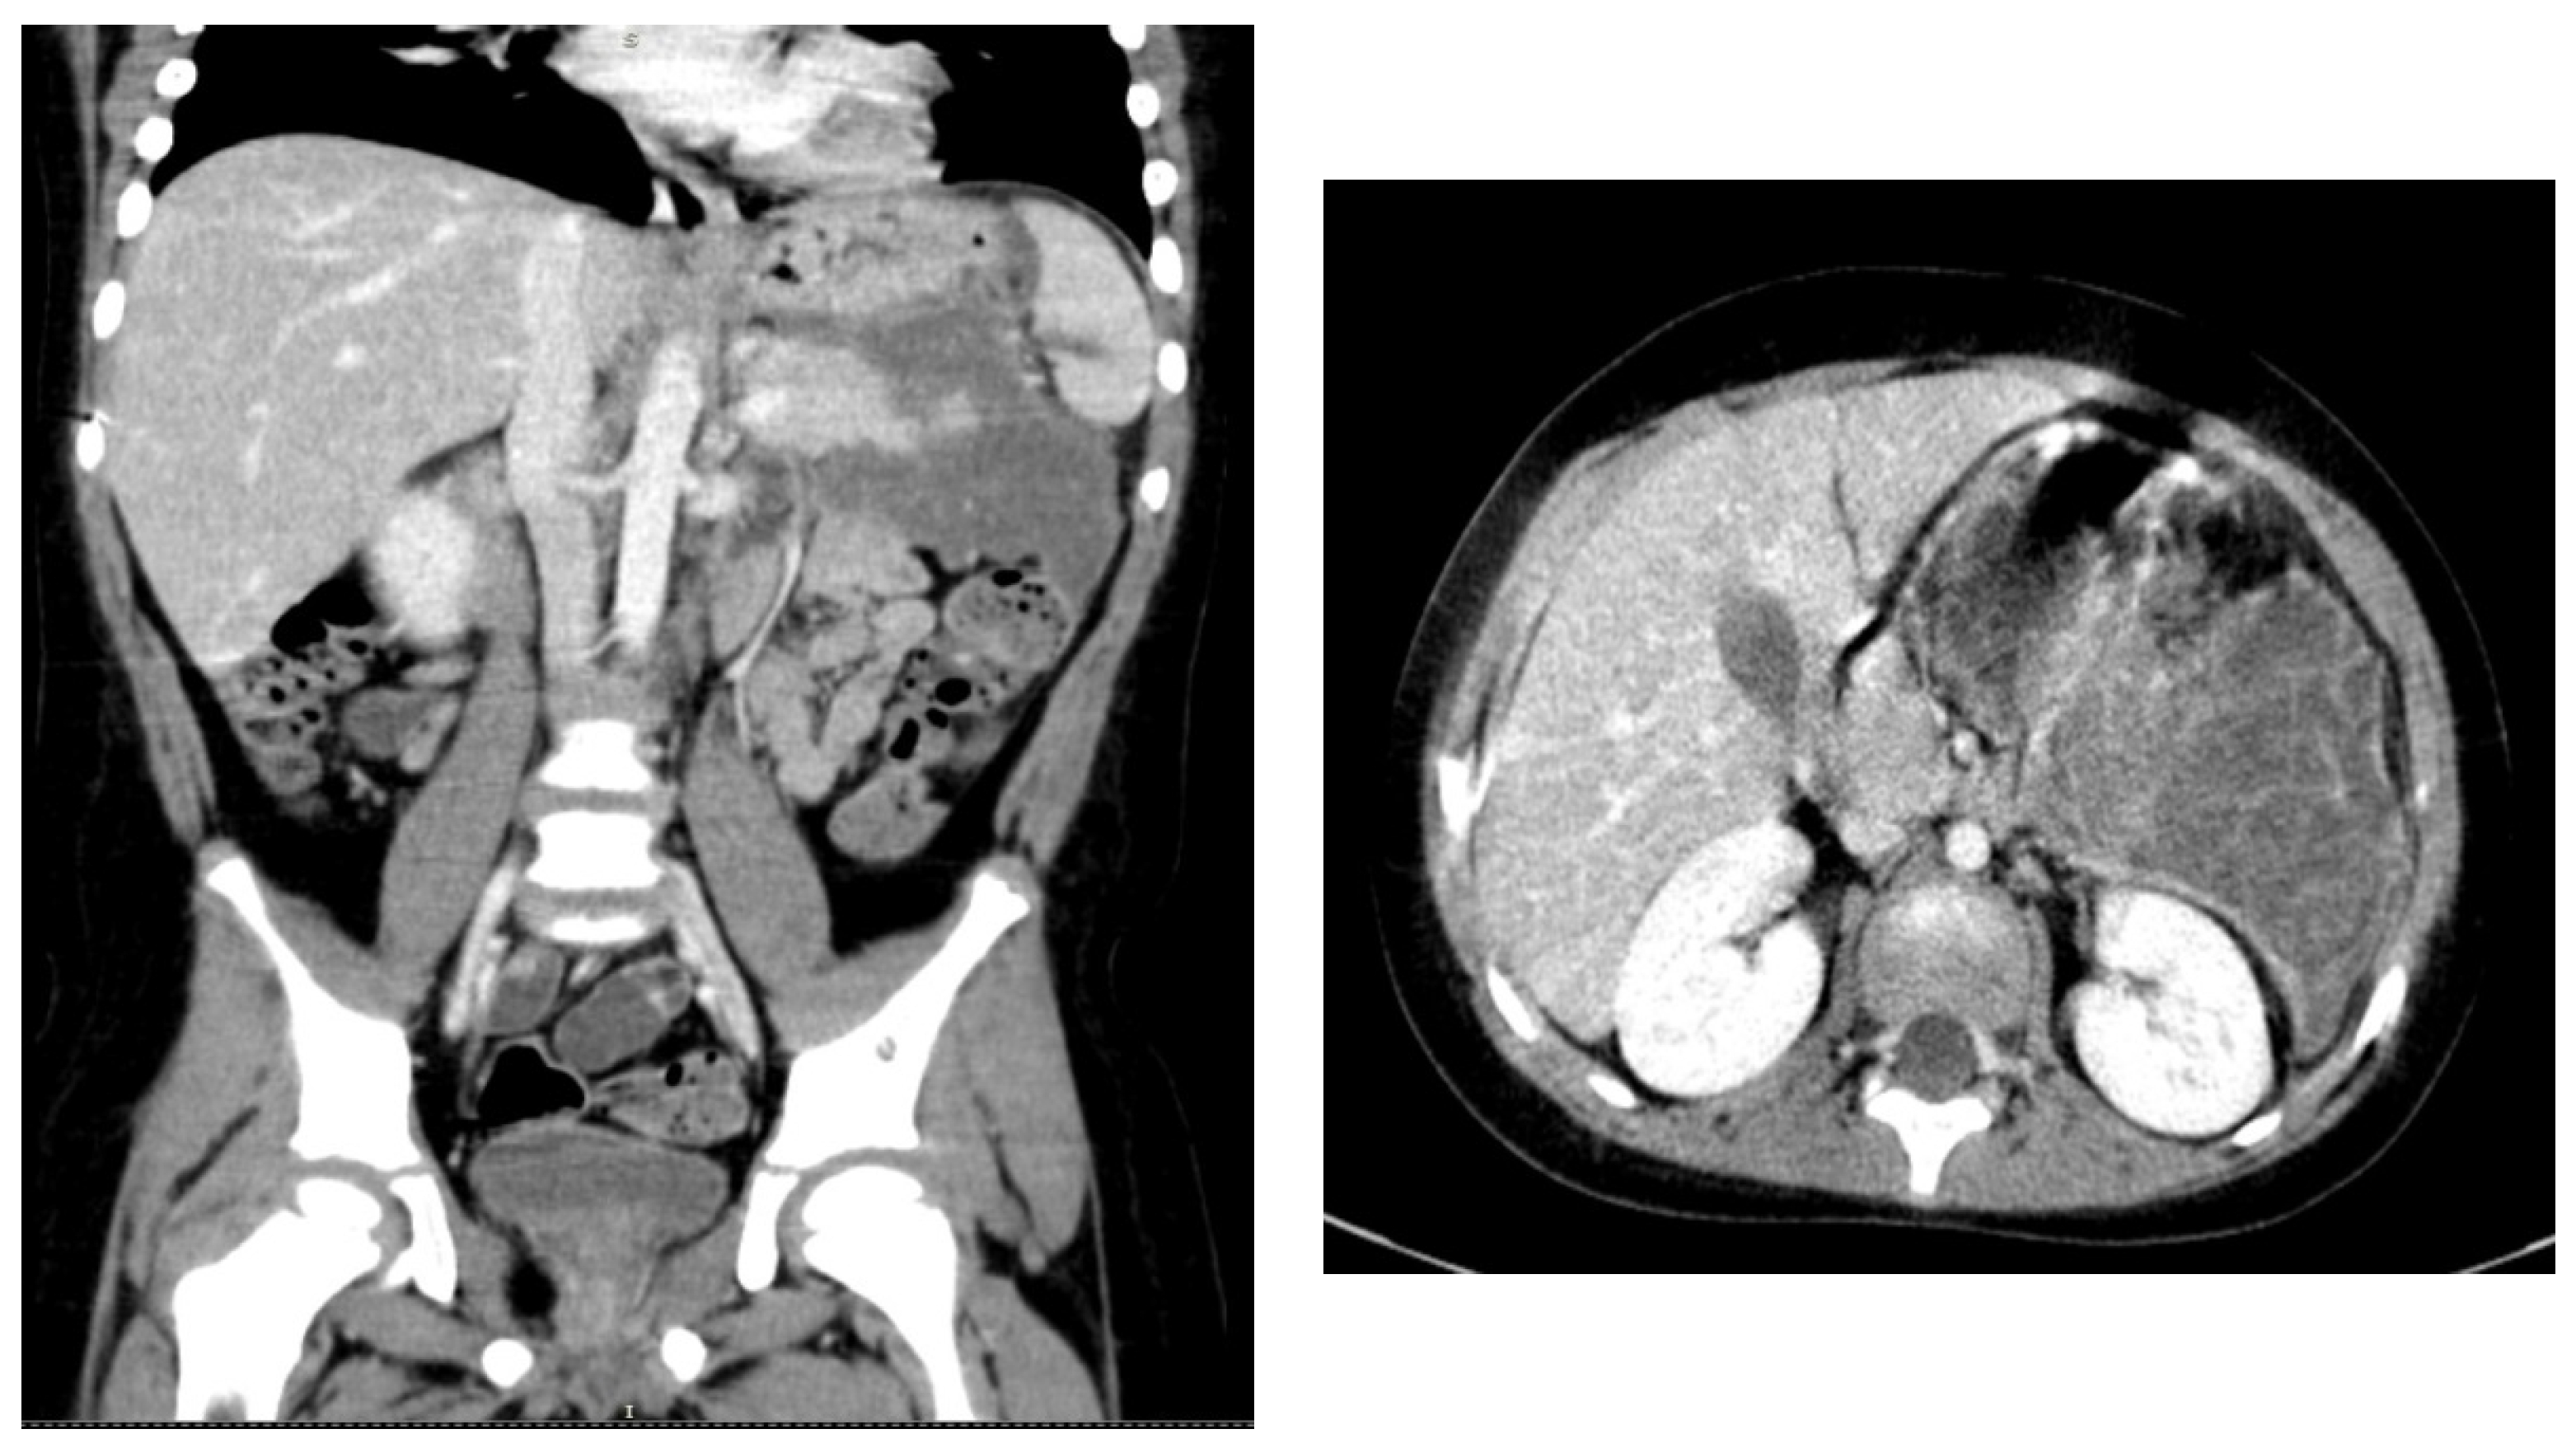

2. Case Report